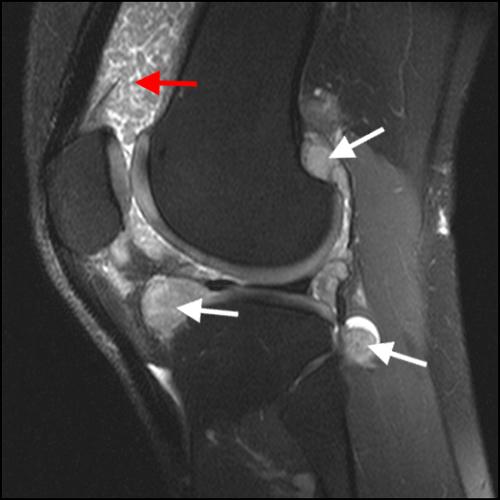

Synovial chondromatosis MRI Sumer's Radiology Blog

The Knee Synovial Osteochondromatosis Elbow Radiology synovial chondromatosis (osteochondromatosis or synovial chondrometaplasia) also known as. multiple rounded partially calcified foci anterior to the distal humerus and elbow joint. imaging plays a vital role in the diagnosis and management of synovial osteochondromatosis, a proliferative. synovial osteochondromatosis is also known as reichel syndrome which is characterized by synovial metaplasia resulting in. the definitive. Synovial Osteochondromatosis Elbow Radiology.